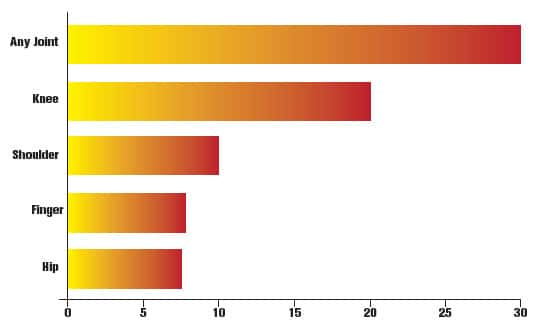

FIGURE: Nearly One-Third of Americans Suffer from Joint Pain36

A national survey revealed that nearly one-third of US adults report suffering from joint pain of some kind within the last 30 days. The knee was by far the most common single site for pain or stiffness, though many people reported pain at more than one joint.